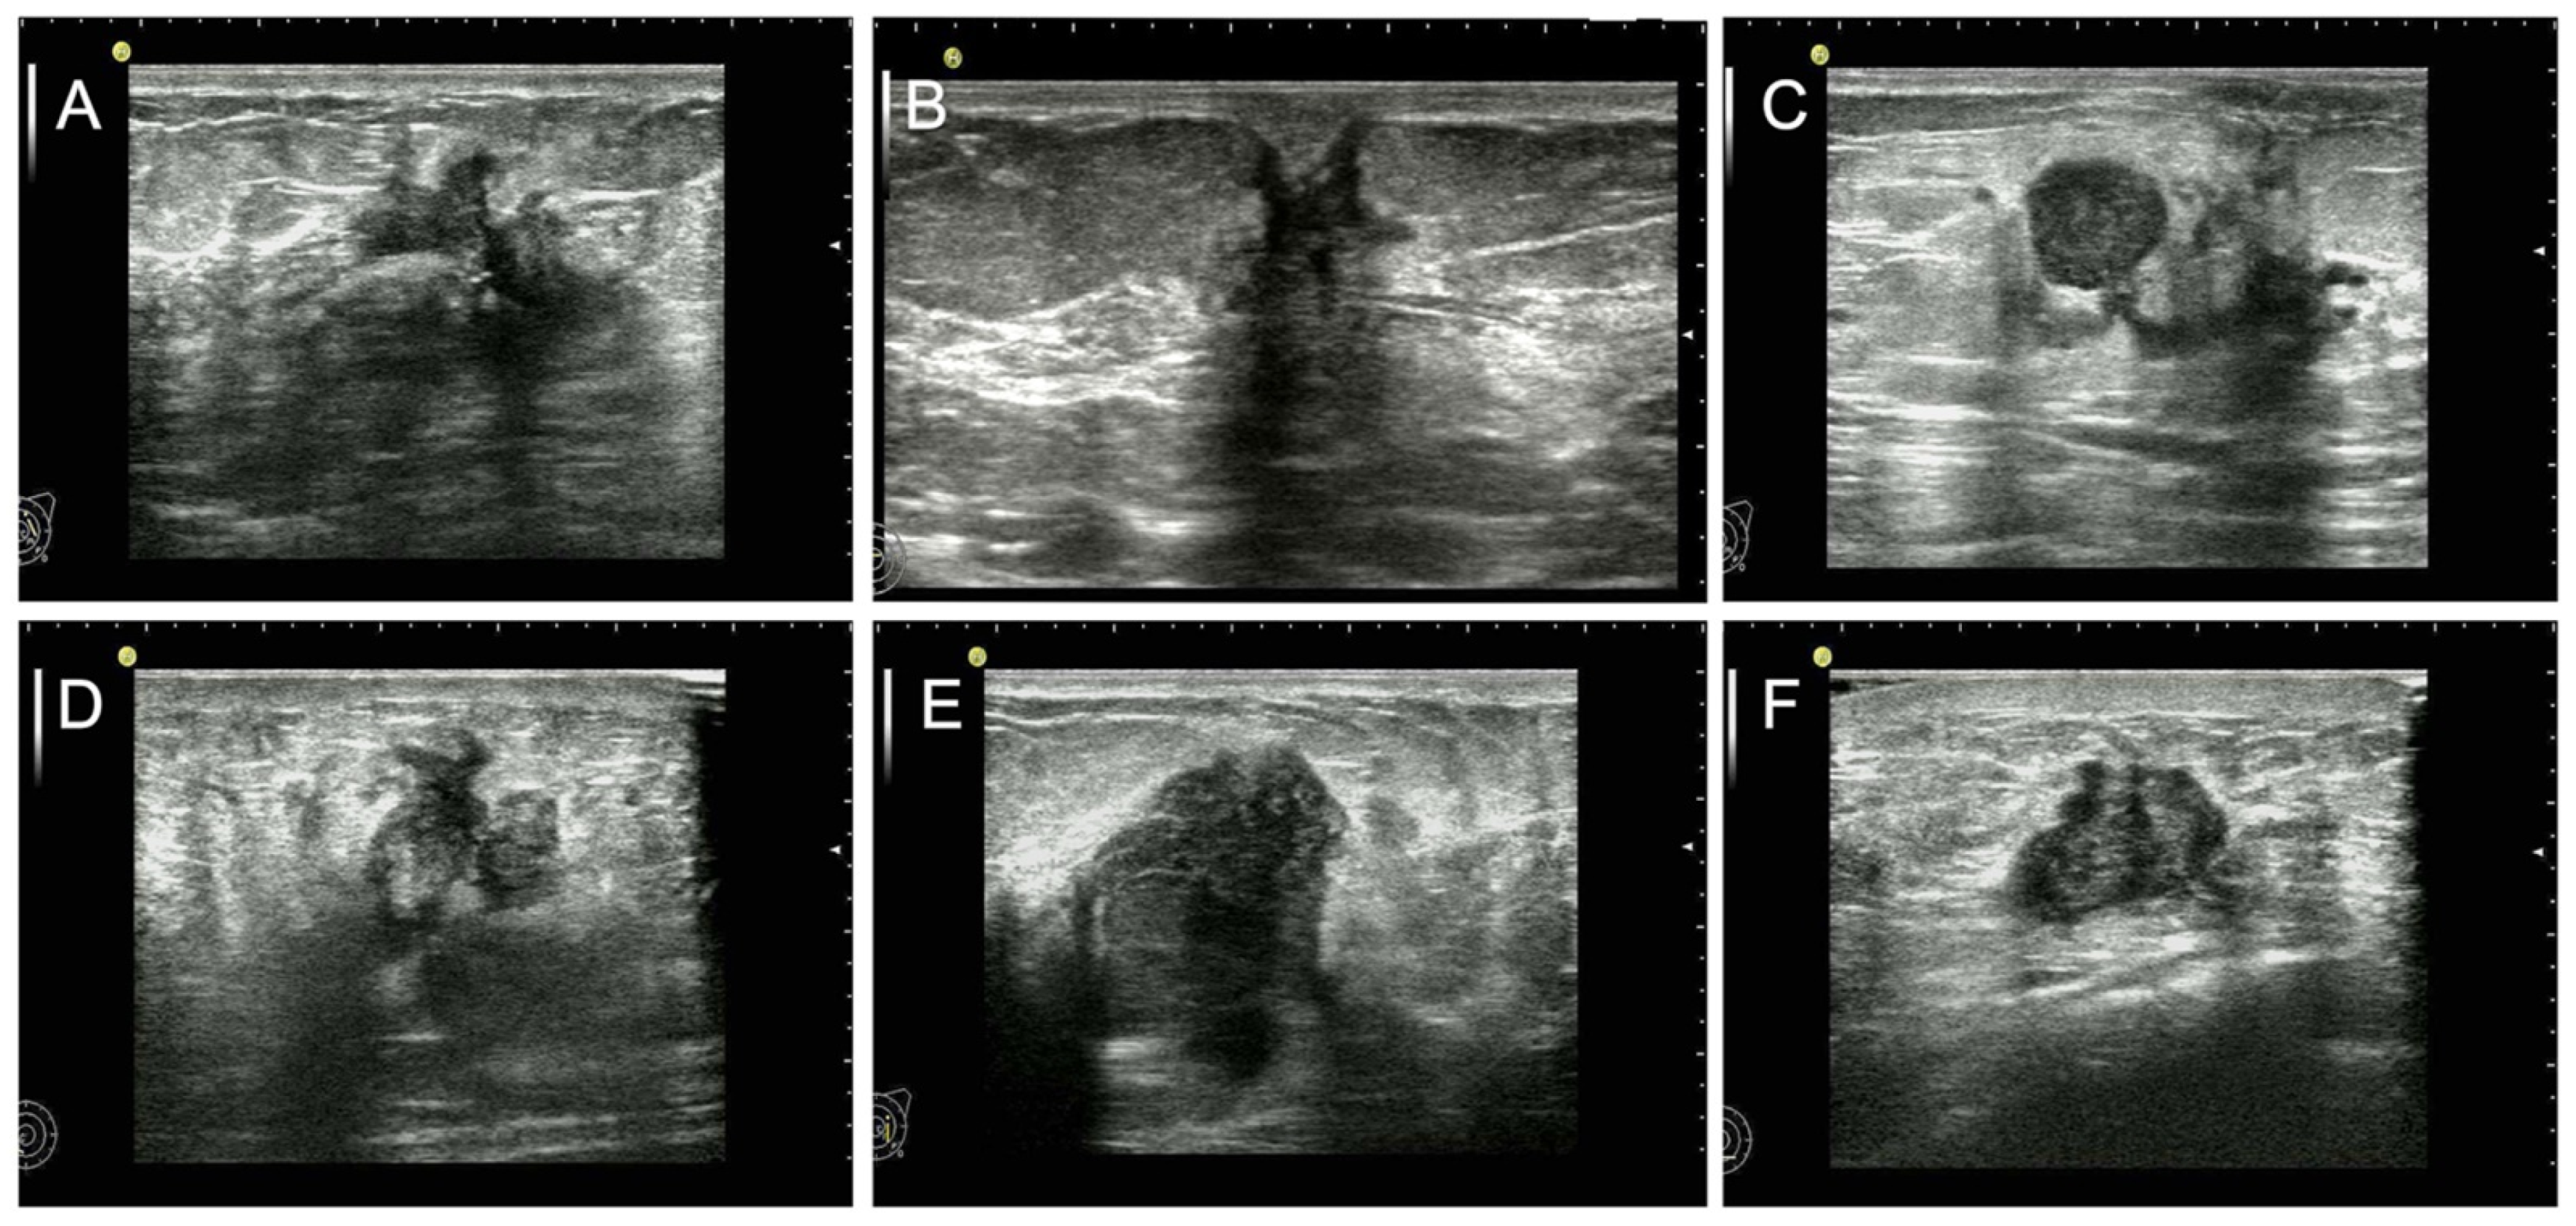

- Li, Z.; Tian, J.; Wang, X.; Wang, Y.; Wang, Z.; Zhang, L.; Jing, H.; Wu, T. Differences in multi-modal ultrasound imaging between triple negative and non-triple negative breast cancer. Ultrasound Med. Biol. 2016, 42, 882–890. [Google Scholar] [CrossRef]

- Zhang, L.; Li, J.; Xiao, Y.; Cui, H.; Du, G.; Wang, Y.; Li, Z.; Wu, T.; Li, X.; Tian, J. Identifying ultrasound and clinical features of breast cancer molecular subtypes by ensemble decision. Sci. Rep. 2015, 5, 11085. [Google Scholar] [CrossRef]

- Guo, Q.; Dong, Z.; Zhang, L.; Ning, C.; Li, Z.; Wang, D.; Liu, C.; Zhao, M.; Tian, J. Ultrasound features of breast cancer for predicting axillary lymph node metastasis. J. Ultrasound Med. 2018, 37, 1354–1353. [Google Scholar] [CrossRef] [Green Version]

- Guo, Q.; Zhang, L.; Di, Z.; Ning, C.; Dong, Z.; Li, Z.; Wang, D.; Liu, C.; Zhao, M.; Tian, J. Assessing risk category of breast cancer by ultrasound imaging characteristics. Ultrasound Med. Biol. 2018, 44, 815–824. [Google Scholar] [CrossRef]

- Malherbe, K.; Bresser, P. Association between ultrasound morphologic features and histopathological findings of lobular carcinoma. J. Med. Radiat. Sci. 2019, 66, 177–183. [Google Scholar] [CrossRef] [PubMed] [Green Version]

- Stavros, A.T.; Thickman, D.; Rapp, C.L.; Dennis, M.A.; Parker, S.H.; Sisney, G.A. Solid breast nodules: Use of sonography to distinguish between benign and malignant lesions. Radiology 1995, 196, 123–134. [Google Scholar] [CrossRef] [PubMed] [Green Version]

- Li, Z.; Ren, M.; Tian, J.; Jiang, S.; Liu, Y.; Zhang, L.; Wang, Z.; Song, Q.; Liu, C.; Wu, T. The differences in ultrasound and clinicopathological features between basal-like and normal-like subtypes of triple negative breast cancer. PLoS ONE 2015, 10, e0114820. [Google Scholar] [CrossRef]

- Choi, B. Comparison of ultrasound features with maximum standardized uptake value assessed by 18f-fluorodeoxyglucose-positron emission tomography/computed tomography for prognosis of estrogen receptor+/human epithelial growth factor receptor 2- breast cancer. Ultrasound Q. 2021, 38, 18–24. [Google Scholar] [CrossRef]

- Wang, H.; Yao, J.; Zhu, Y.; Zhan, W.; Chen, X.; Shen, K. Association of sonographic features and molecular subtypes in predicting breast cancer disease outcomes. Cancer Med. 2020, 9, 6173–6185. [Google Scholar] [CrossRef]

- Wang, H.; Zhan, W.; Chen, W.; Li, Y.; Chen, X.; Shen, K. Sonography with vertical orientation feature predicts worse disease outcome in triple negative breast cancer. Breast 2020, 49, 33–40. [Google Scholar] [CrossRef] [Green Version]